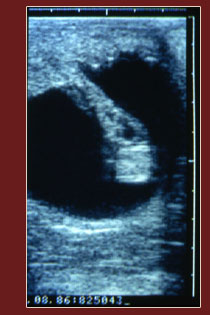

Individual Experience with Ultrasounding In-House Mares |

Description: A herd of 15 to 20 in-house mares will be available daily (3.5 hour sessions) for palpation/ultrasound exams. Participants are welcome to utilize these mares throughout a 2- or 4- day period to gain experience with palpation and ultrasonographic techniques. This course is held at Equine Reproduction Concepts, LLC, a reproduction facility located in Amissville, Virginia. For additional information call 540-937-9832 or e-mail info@equinereproduction.com.